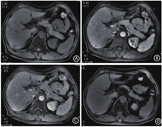

查体:T:36.7℃、P:98次/min、R:20次/min、BP:133/86 mmHg。神志清楚,全身皮肤未见异常。全身浅表淋巴结未触及肿大,心肺查体无异常。腹平软,无压痛,无反跳痛,未扪及包块。肝脾肋下未触及。墨菲氏征(-)。麦氏点无压痛。移动性浊音(-),肝肾区无叩击痛,肠鸣音5次/min。双下肢无浮肿。病理征阴性。入院查上腹部磁共振成像(MRI)平扫+增强(图2)示:肝右叶包膜下可见两枚结节灶,大者直径约为1.7 cm,T1加权像(T1-weighted image, T1WI)低信号,脂肪抑制T2加权成像(fat-suppressed T2-weighted imaging,FST2WI)高信号,形态欠规则、边界欠清,信号欠均匀,增强扫描病灶动脉期可见环形强化、片状强化,并呈持续渐进强化,延迟期呈高信号,提示肝右叶下段包膜下富血供结节,考虑肝内局灶性结节增生可能,恶性病变待排。为进一步明确肝内结节性质,于2020-05-18行彩超引导下肝内低回声结节穿刺活检术,病理示(图3):慢性活动性肝炎,肝细胞内胆汁淤积,部分肝小叶破坏消失,纤维组织增生,内见大量浆细胞及嗜酸性粒细胞浸润,形成嗜酸细胞肉芽肿。免疫组化染色:CK8(肝细胞+),CK7(胆管+),CD68(-),Hepatocyte(肝组织+),CD34(血管+),Desmin(血管+,余-),SMA(血管+,余-),EMA(-),ALK(-),CD117(-),DOG-1(-)。特殊染色:过碘酸-雪夫染色(肝组织+,未查见真菌-),铁染色(局灶+),铜染色(部分肝细胞+),六胺银染色(未查见真菌-),W-S(未查见真菌-)。网状纤维嗜银染色:残余肝组织网状纤维支架走向基本正常,部分肝小叶结构完整破坏,网状纤维增生杂乱排列。

注:A~C:治疗前,肝右叶包膜下可见两枚结节灶,大者直径约为1.7 cm,形态欠规则、边界欠清,信号欠均匀,增强扫描病灶动脉期可见环形强化、片状强化,呈持续渐进强化,延迟期呈高信号; D:治疗3个月后复查MRI示肝包膜下结节信号影较前明显缩小

患者多次查血象提示外周血嗜酸性粒细胞显著增高,否认家族遗传及类似病史,否认疫区疫水接触史、生食海产品史以及肝炎、结核等传染病史,无寄生虫感染证据,入院查肝肾功能、心肌酶、肿瘤标志物、粪便寄生虫、乙型和丙型肝炎病毒血清学标志物、梅毒螺旋体抗体、人类免疫缺陷病毒抗体、肿瘤标志物、血清电泳蛋白、尿本周蛋白、自身免疫检查、肺部CT平扫、心电图等均未见明显异常,可排除肿瘤、传染病、寄生虫感染、自身免疫性疾病等继发病因,患者无发热、淋巴结肿大、脾大等血液系统疾病表现,考虑血液系统肿瘤可能性小,建议完善骨髓穿刺、分子遗传学检测以明确,患者表示拒绝。结合外周血象、食管及肝脏病理,考虑嗜酸性粒细胞增多综合征(hypereosinophilic syndrome, HES)食管、肝浸润,为排除肠道嗜酸性粒细胞浸润,进一步行肠镜检查提示结肠管状腺瘤。后续予以经验性激素治疗(甲泼尼龙片24 mg每天1次,维持2个月后,每周减4 mg,直到停药),3个月后患者吞咽困难症状缓解,复查外周血嗜酸性粒细胞计数正常,复查MRI示肝脏病灶较前明显缩小(图2),目前患者小剂量激素维持治疗,仍密切随访中。